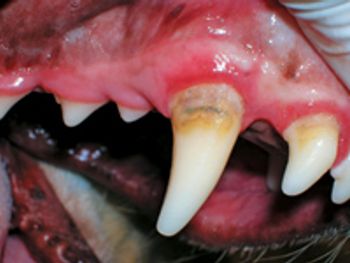

Tooth resorption is the most common dental problem in cats, with studies worldwide showing a prevalence rate (in cats presented for dental problems) of up to 75%.